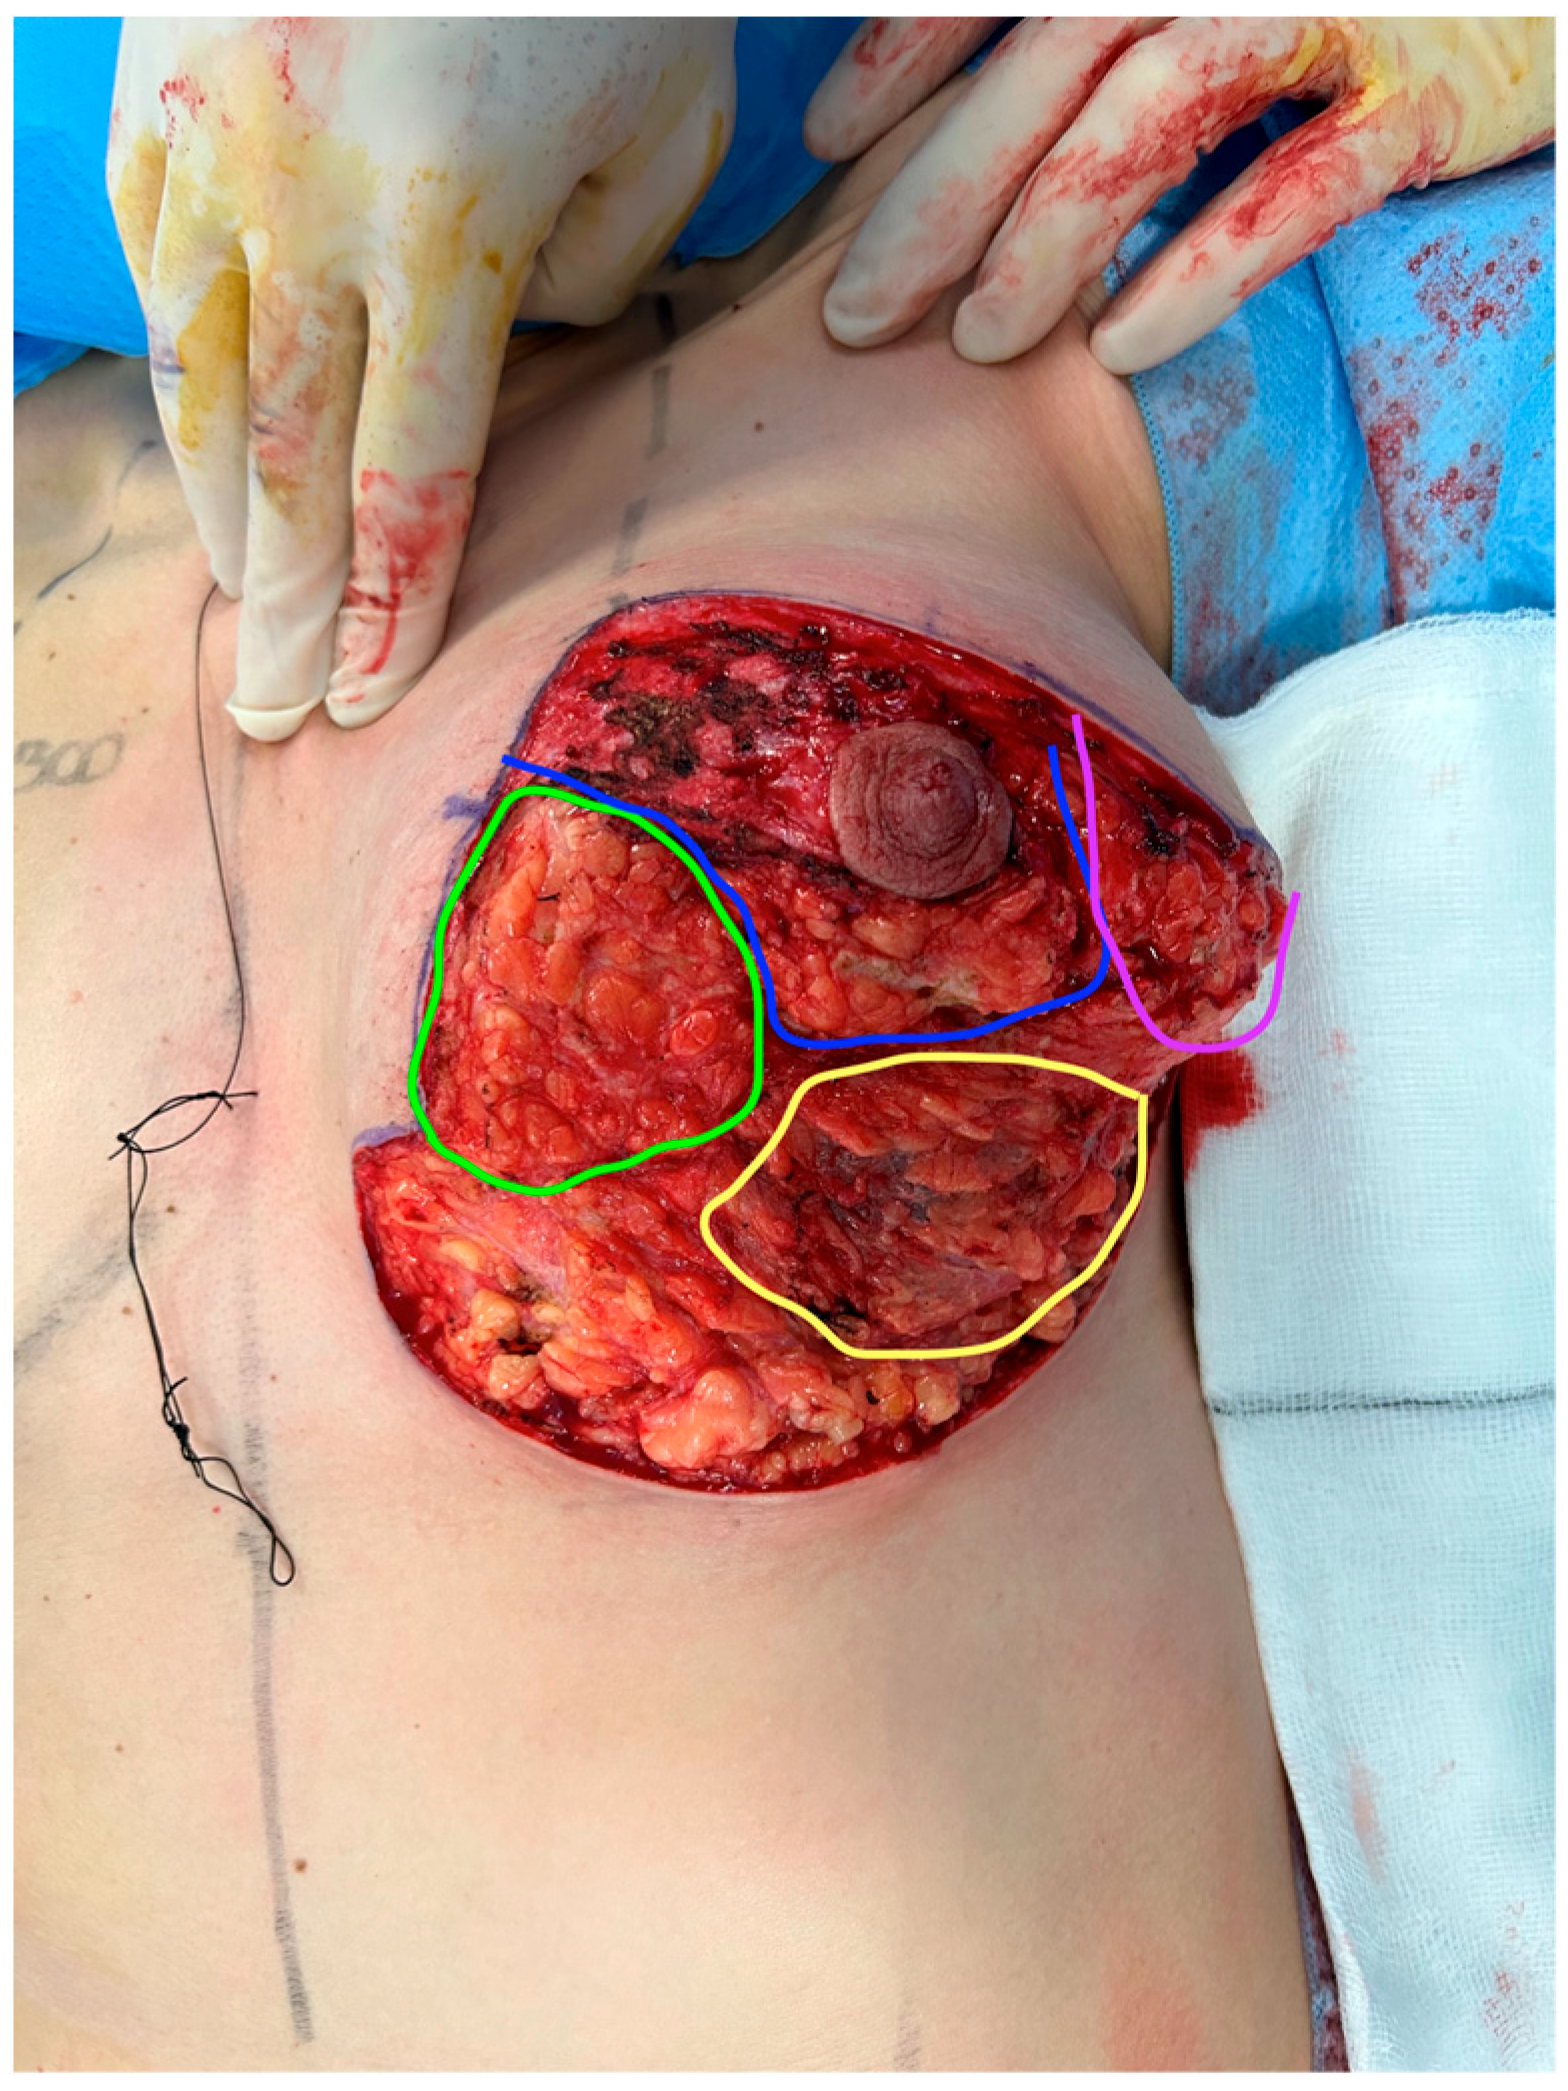

The findings from our pre-operative and post-operative questionnaires show that patients, overall, reported a statistically significant improvement in satisfaction across all six question parameters (

Table 2). This supports the effectiveness of breast reduction plus implants in attaining an outcome desired by patients (

Figure 1 and

Figure 2).